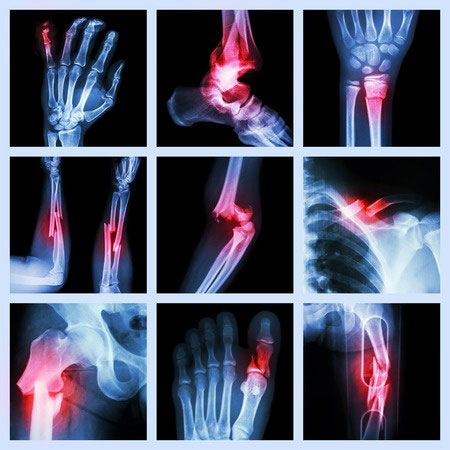

W opublikowanym badaniu analizowano dane ponad 130 000 kobiet w wieku 40-64 lat, które przyjmowały SSRI między 1998 a 2010 rokiem. Kobiety te nie miały wcześniej zaburzeń psychiatrycznych. Do najczęściej stosowanych u nich leków należały m.in. citalopram, escitalopram, fluoksetyna, paroksetyna i sertalina. W grupie kontrolnej wykorzystano informacje ponad 230 000 kobiet w odpowiednim wieku, którym przepisywano H2-blokery albo inhibitory pompy protonowej. Analiza zebranych danych wykazała, że ryzyko złamań było znacząco wyższe w pierwszej grupie. Odsetek kobiet doświadczających ich miał być 76% wyższy wśród osób stosujących SSRI przez rok, 73% wyższy po 2 latach od rozpoczęcia leczenia oraz 67% wyższy po 5 latach.